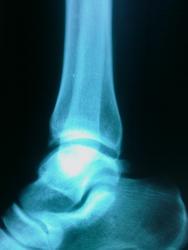

Девушка 20 лет обратилась в травмпункт на периодические боли в левом гсс. факта травмы не было. О чем можно думать? -остеохондропатия, - остеомиелит, - tbc, что-то еще?

В перечне остеохондропатий есть остеохондропатия блока таранной кости ( Вейса (Вайса) (Weiss) - Мюллера (Muller) болезнь ), относится к частичным клиновидным остеохондропатиям (по типу болезни Кенига).

Болезнь Мюллера Вейса это немного другое, поражается ладьевидная кость. Смотрите статью в вложениях. В данном случае я думаю о аваскулярном некрозе, рекоммендовал бы МРТ.

Аваскулярный некроз и остеохондропатия (асептический некроз) - это почти одно и тоже по большому счёту. Кроме того, в данном наблюдении, мы имеем так называемый "законченный случай" и признаки уже развивающегося деформирующего артроза. В данном случаее целесообразнее начинать лечение, ибо артроз, безусловно будет прогрессировать.

А есть-ли боковой снимок?

добавил

Случай конечно редчайший, прямо "эксклюзив". Я лично такого не встречал. Возможно коллеги, что-то скажут.

Весьма похоже уважаемая коллега, и очень кажется убедительным, именно в сравнении с болезнью Кенига.

В данном случае я думаю о аваскулярном некрозе, рекоммендовал бы МРТ.

Я и имела ввиду асептический некроз. Возможно, в литературе напутано с названиями этой патологии. Еще встречала и такие названия - болезнь Диаза (Diaz), болезнь Диаза-Вейса-Мюллера, асептический некроз таранной кости, рассекающий остеохондроз тела таранной кости, остеохондрит таранной кости.

Я бы не постеснялся трактовать данные случаи как остеохондропатии, по типу б-ни Кенига.